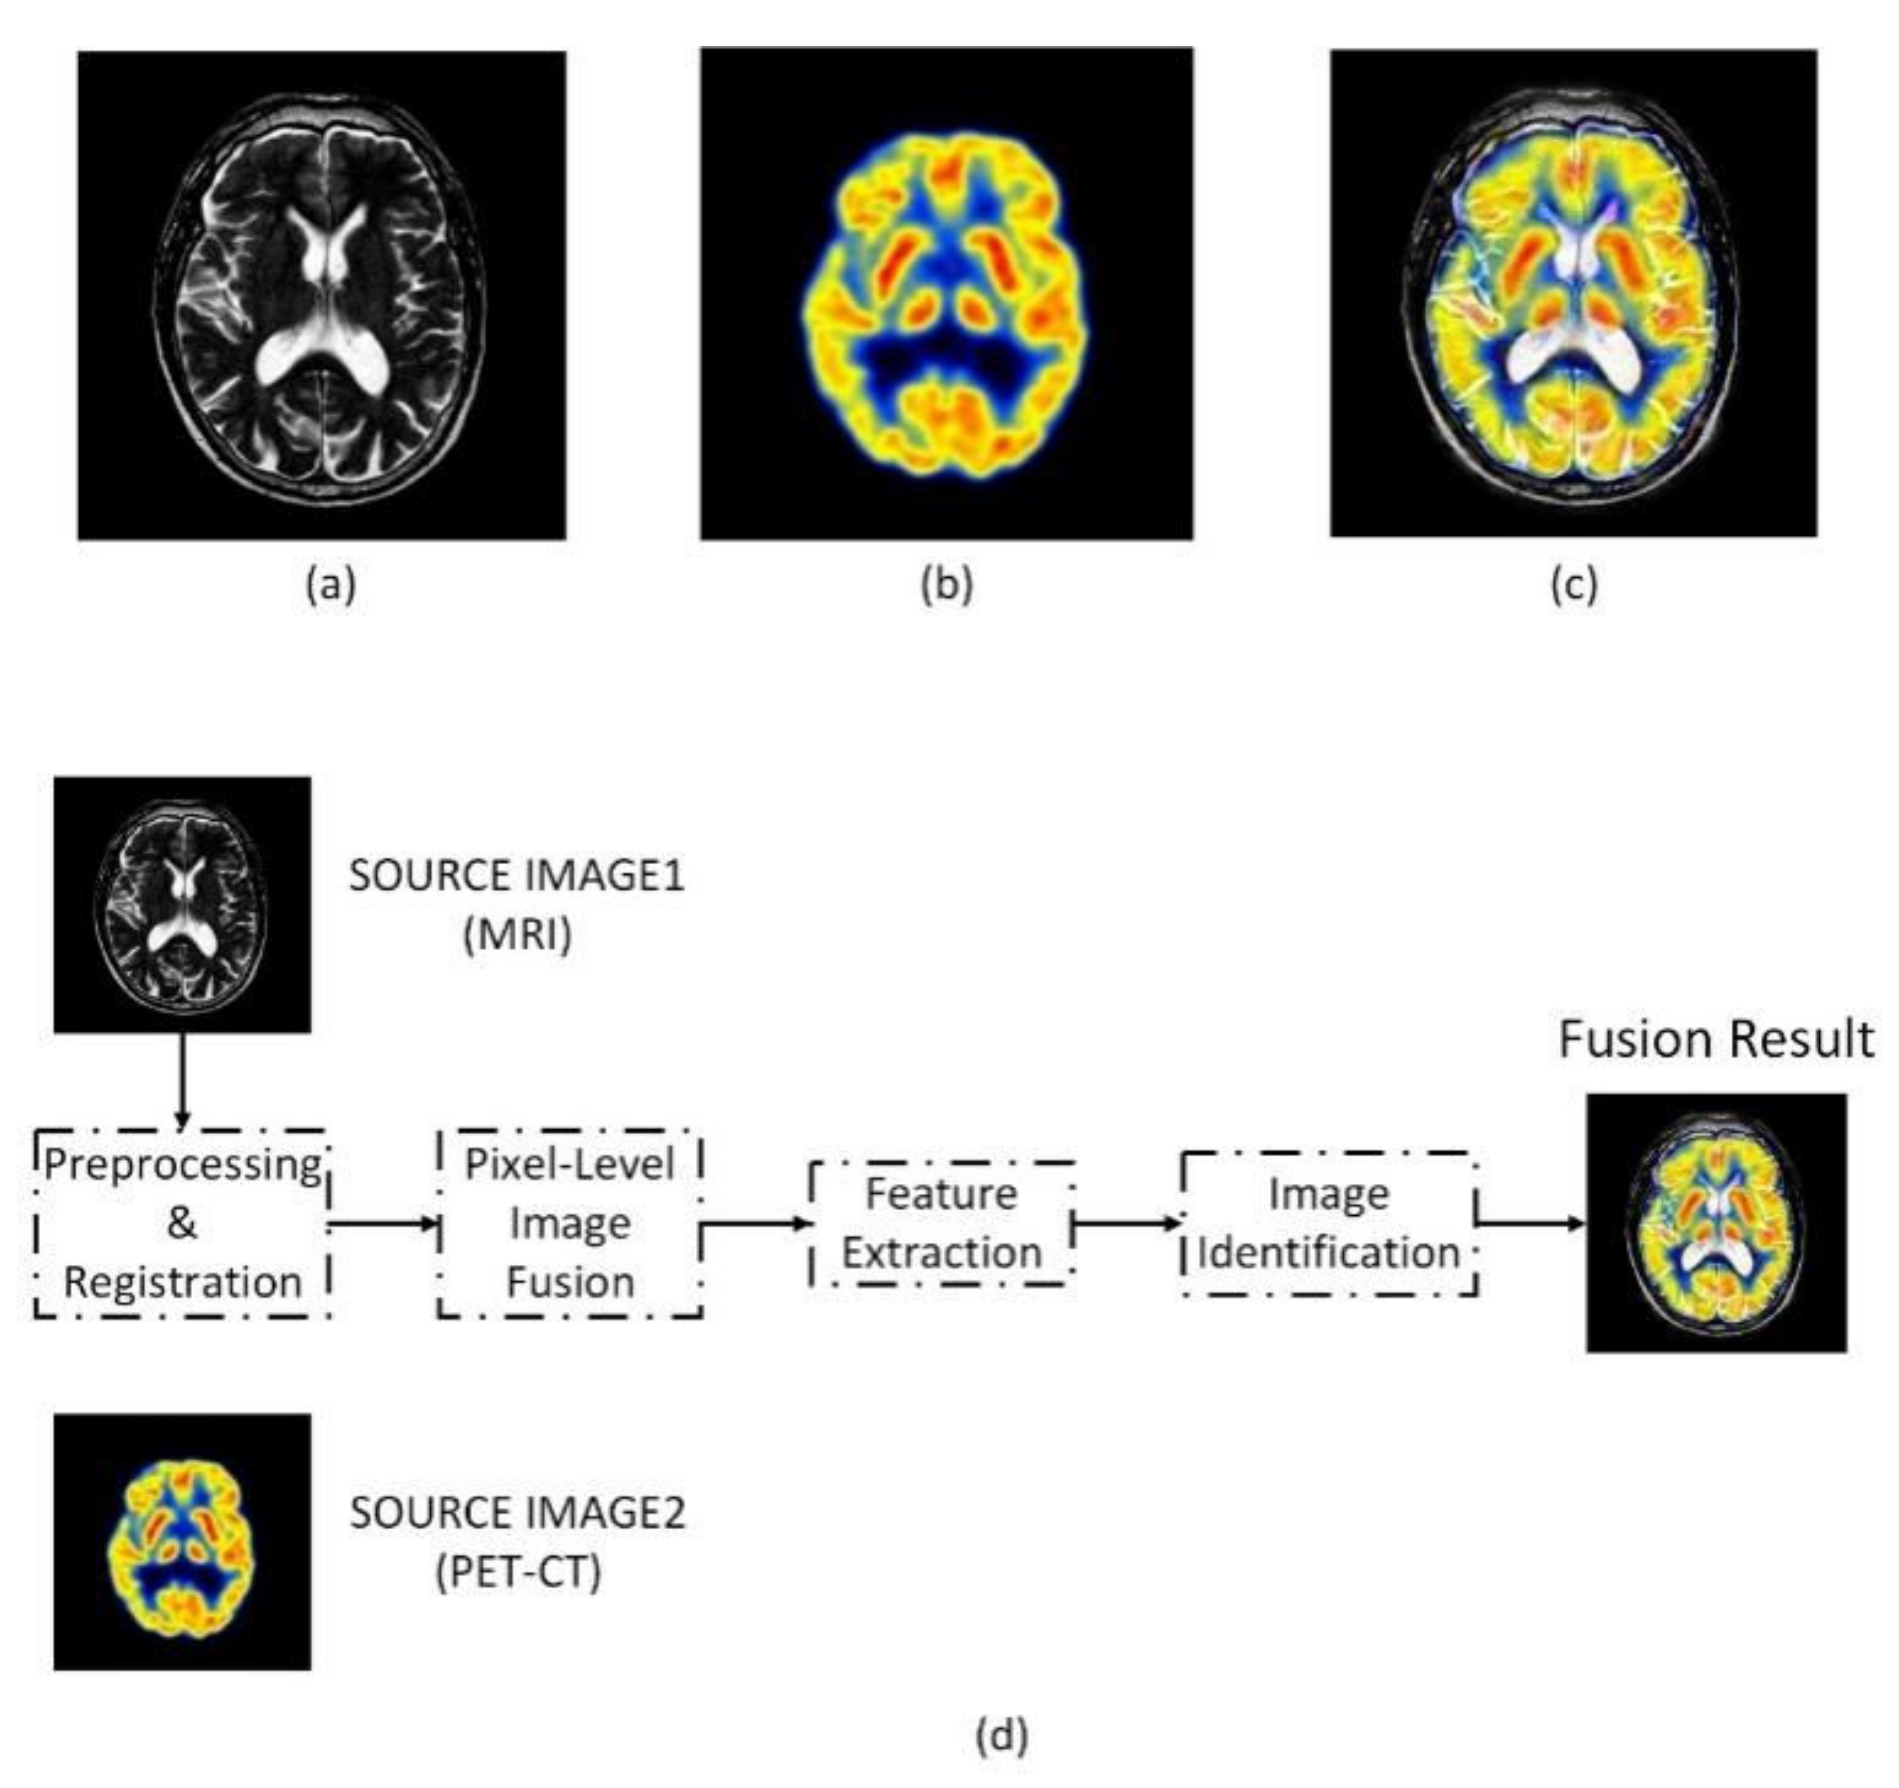

1.2. Multimodal Image Fusion Technology

2.4. Multimodal Pixel-Level Image Fusion

3.1. Multimodal Image Fusion Results